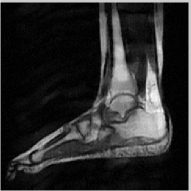

The reconstructions of an ankle image from its 4 fold Cartesian undersampled Fourier data, corrupted with zero mean complex Gaussian noise with a standard deviation σ=10𝜎10\sigma=10, are shown in Fig. 5. This is a really challenging case since the 1-D downsampling pattern is considerably less efficient than the 2-D random pattern used in the previous experiment. We observe that the non-local algorithm provides better reconstructions than the other schemes. Specifically, the TV scheme results in patchy artifacts. The DLMRI scheme results in blurring and loss of details close to the heel. The details are relatively better preserved close to the finger since there are no structures above or below it that aliases to it. By contrast to the classical algorithms, the degradation in performance of the non-local algorithm is comparatively small. The quantitative comparisons of the algorithms on this setting using different images are shown in the top section of Table IV.

Refer to caption

(a) Original

(b) DLMRI, SNR=12.96

(c) TV, SNR=15.02

(d) NLS, SNR=18.52

(e) Sampling pattern

(f) DLMRI error

(g) TV error

(h) NLS error

Figure 5: Comparison of the algorithms in the presence of noise. We consider the recovery of a 256×256256256256\times 256 MRI ankle image from its Cartesian Fourier sampling pattern (shown in (e)), contaminated by zero mean complex Gaussian noise with standard deviation σ=10𝜎10\sigma=10. The top row shows the original and reconstructed images, while the error images scale by a factor of five are shown in the bottom row. This is a challenging case due to the high 1-D undersampling factors and noise. We observe that the NLS scheme provides the best reconstructions with minimal alias artifacts.